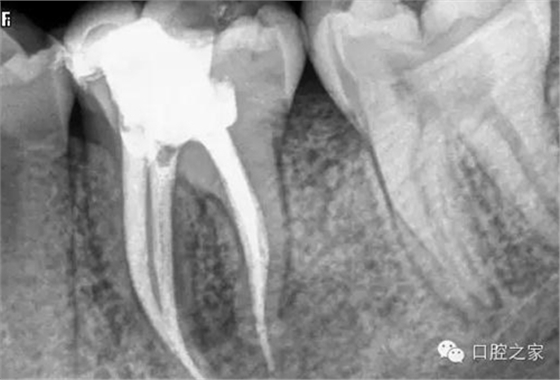

(4)根管欠填或超填 良好的根管充填是適填,無(wú)論是去髓術(shù)或根管治療,只要根管經(jīng)過(guò)有效的藥物消毒,允許少量欠填或超填(0.5~1.0㎜)。但如欠填過(guò)多,近根尖孔處形成死腔,可能導(dǎo)致組織液滯留,尤其是根尖周有炎癥者,帶有細(xì)菌的液體回流積聚,可繼續(xù)成為感染源,使根尖周病變難以愈合。而超填過(guò)多的牙膠尖難以被組織吸收,同樣會(huì)影響病變的愈合。

蘸一般藥液的棉捻或紙尖X 線片難以顯影,只有在根尖切除或拔除患牙后才能確診。但蘸有碘仿等X線阻射藥物的棉捻在照片上則易顯影(圖3)。此外,行樁冠修復(fù)的患牙,在釘?shù)李A(yù)備時(shí)如操作失誤,也可將牙膠尖推出根尖孔,導(dǎo)致治療失敗。